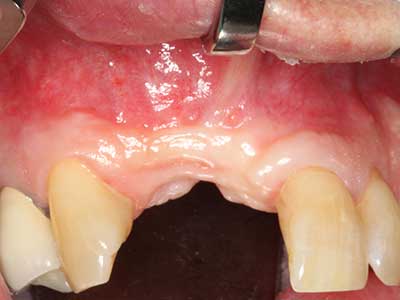

Il tessuto osseo non è semplicemente una struttura minerale, ma contiene anche una percentuale significativa di fibre di collagene. Ciò significa che non possiede solo una buona forza di compressione, ma anche un certo livello di flessibilità che è possibile sfruttare durante l'esecuzione degli accrescimenti di osso. Nella procedura di espansione classica con incisione ossea, la cresta alveolare atrofizzata viene incisa longitudinalmente ed espansa con cautela dopo aver raggiunto una profondità di osteotomia adeguata (figg. 13-16), idealmente senza una sostanziale rimozione del periostio (Brugnami, Caiazzo et al. 2014, Stricker, Fleiner et al. 2014). I sistemi a piastra e vite con distanza di espansione incrementale si sono dimostrati efficaci nella separazione delle due lamelle ossee restando al di sotto della soglia di frattura. In generale, sono richieste larghezze dell'osso residuo di almeno 3-4 mm (Chiapasco, Zaniboni et al. 2006) per garantire un'adeguata flessibilità e una copertura sufficiente dell'osso per gli impianti futuri. Se necessario, un'osteotomia di rilascio verticale su uno o più lati può migliorare la flessibilità. Una combinazione con ulteriori tecniche di accrescimento, in particolare dal lato buccale, è stata descritta come un'alternativa alla tecnica classica.

La procedura di incisione è particolarmente atraumatica e non comporta una perdita significativa di dimensione durante l'utilizzo delle seghe piezoelettriche, così come non si notano differenze rilevanti tra impianti in mandibole incise e impianti in una cresta alveolare senza deficit osseo (Chiapasco, Zaniboni et al. 2006, Danza, Guidi et al. 2009). Una sufficiente irrigazione continua è essenziale, tuttavia, in particolare con incisione profonda e localmente ristretta, per prevenire la sollecitazione termica nelle regioni apicali dell'osteotomia.